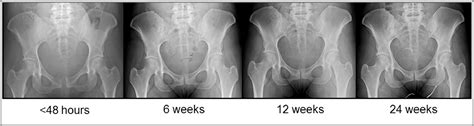

Pubic Symphysis Separation and Regression in Vaginal versus Cesarean